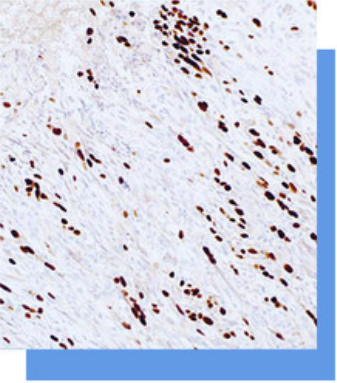

SOX-10抗体试剂

SOX-10是-一个参与神经嵴和周围神经系统发

育的基因,在黑色素细胞、肌上皮细胞、支气管和

乳腺的雪旺细胞中表达,是黑色素瘤的敏感标志物,

用于神经嵴来源的肿瘤等方面的研究。